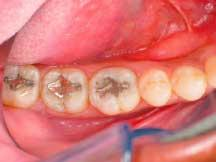

The interproximal areas were verified with floss and, in areas where any flash existed, a 12-B blade was used at the gingival margin in a gentle, carving motion to remove it (Figure 5). To reproduce the natural shape and anatomy of the teeth, a series of fine and super-fine diamond finishing burs (Axis Dental Corporation) were used. The occlusion was then checked and, where necessary, a pointed bur was used to reform the anatomy following any occlusal adjustments.

The rubber dam was removed, occlusion was checked and adjusted, and final polishing was completed using a green Jiffy polishing cup (Ultradent Products, Inc.) and Jiffy bristle brush. To best polish the gingival areas, a finishing strip (Epitex Strip) was used. Figure 6 shows the completed direct composite posterior restorations.